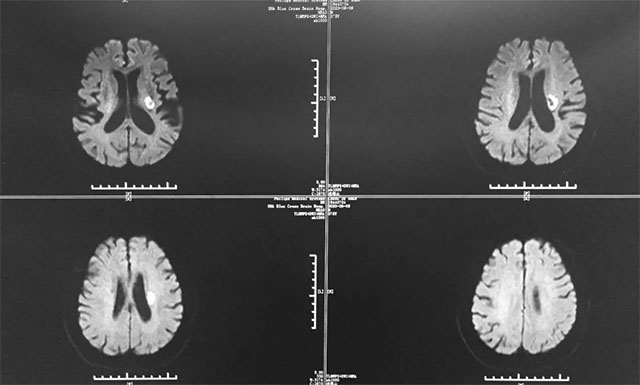

今年5月29日,胡先生正坐在沙發(fā)上看手機(jī),突然感覺自己的右腿有些麻木,當(dāng)時想著肯定是坐著看手機(jī)時間太長了,就沒太在意。第二天下午,他一如既往地去廣場跳舞,當(dāng)時右腿還是有些麻木,但不影響跳舞,可是等到晚上8點多時,他明顯感覺不對勁,右腿麻木癥狀較前加重,遂即就診于當(dāng)?shù)亟K省某醫(yī)院。入院后,患者行頭部CT檢查,根據(jù)影像結(jié)果,患者被診斷為多發(fā)性腦梗,并予以相關(guān)對癥治療。

▲ 胡先生多發(fā)性腦梗,情況不容樂觀

據(jù)戴秀珍主任回憶,胡先生剛?cè)朐簳r其腦梗還是比較嚴(yán)重的,患者屬于多發(fā)性腦梗,并多處血管狹窄,致使其右側(cè)肢體功能障礙。尤其是右側(cè)上肢肢體,近端肢體肌力為2級,其遠(yuǎn)端肢體肌力卻為0級,而且右上肢還伴有神經(jīng)性水腫;其下肢肢體肌力為3級,不能站立和行走,并出現(xiàn)了言語含糊癥狀。